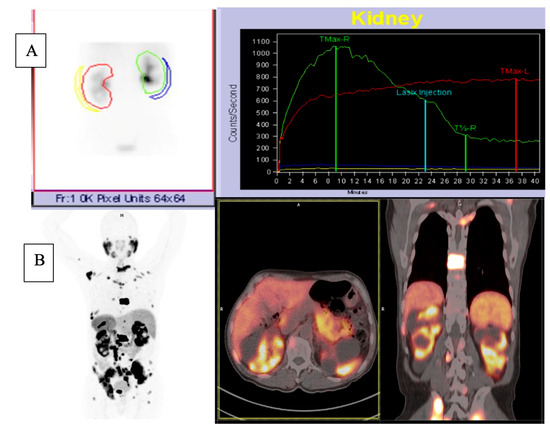

2.1.1. 68Ga-PSMA PET/CT

2.1.2. 68Ga-PSMA PET/CT Image Analysis

2.1.3. 99mTc-MAG3 Renal Scintigraphy